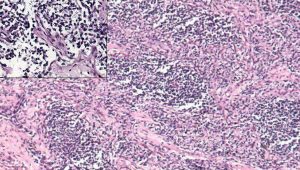

Rhabdomyosarcoma tumor cells. Recent discoveries could contribute to future drug development for this rare childhood cancer.

Other rhabdomyosarcoma research is highlighting a gene called AVIL. In 2020, AVIL was discovered to be involved in glioblastoma, a deadly type of cancer with few treatment options. The authors of a June 2022 study report that AVIL is activated in many pediatric rhabdomyosarcoma tumors. In both glioblastoma and rhabdomyosarcoma, the authors showed that silencing AVIL could kill tumor cells in a dish and prevent tumor growth in mice.